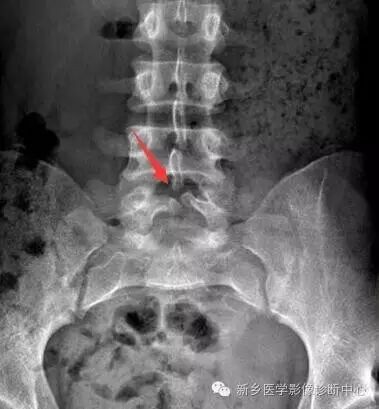

图. 男性,14岁,X线下典型的椎体扇贝样改变